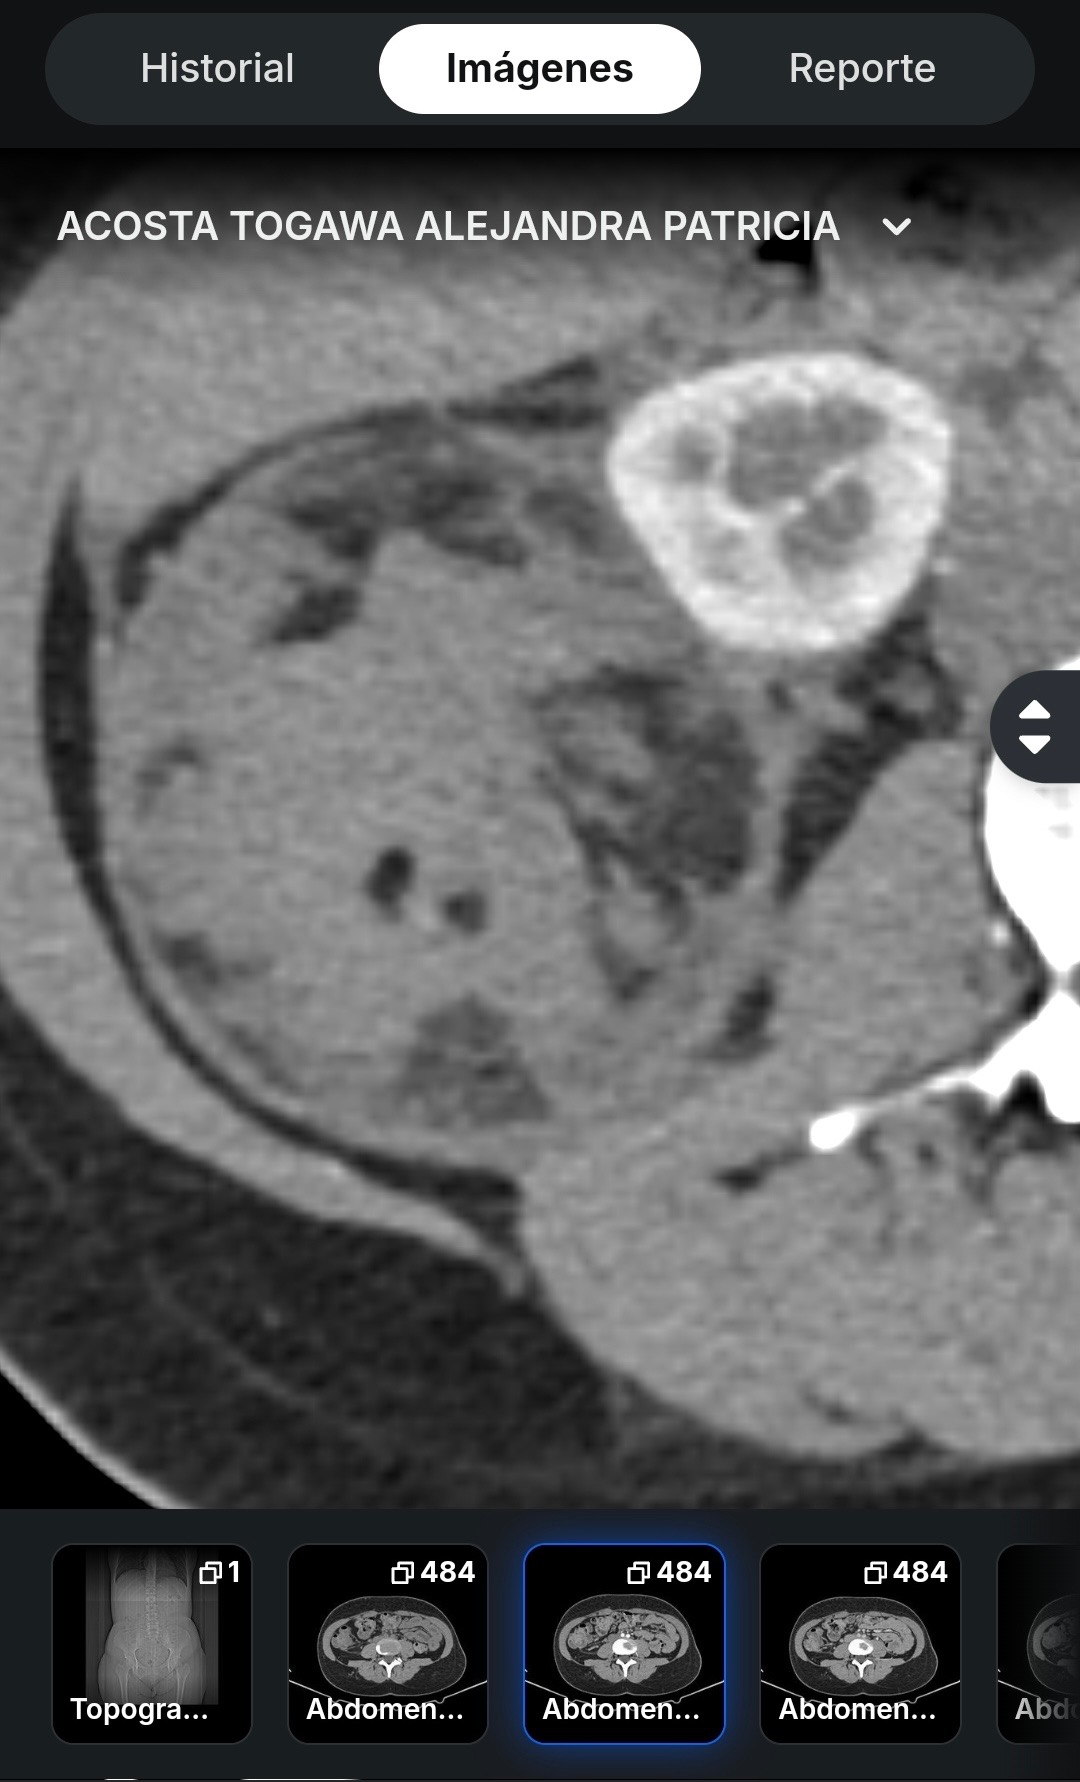

Last month Alejandra had to have emergency surgery, after being rushed to the hospital with internal bleeding and a growth 3 times size of her kidney on her kidney. The surgery was a success, stopped the bleeding and saved her life. 5 days in the hospital and 3 weeks of recovery at home and she was back on her feet. The medical bills for this life saving procedure was $49,000.00

The white circle patch is her kidney pushing against her bladder on the upper right and the big round ball to the left is the cyst that has to get removed before it ruptures and causes internal bleeding once again.